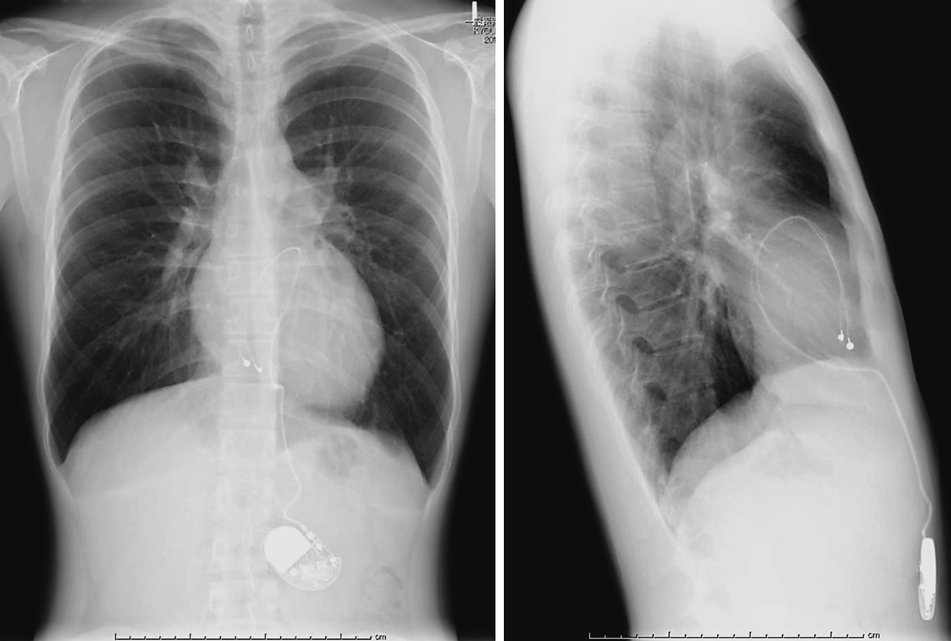

胸部X線

心胸郭比46%,うっ血なし,正面像で心外膜リードは心陰影の内側に偏位し,側面像で右室心尖部の電極から心背側に向かってループを形成していた(Fig. 2).

Pediatric Cardiology and Cardiac Surgery 37(1): 35-41 (2021)

Fig. 2 The chest X-ray on admission

Left: Frontal view (LAO 0°, CRA 0°), Right: Lateral view (LAO 90°, CRA 0°) The epicardial lead encircled the cardiac silhouette.